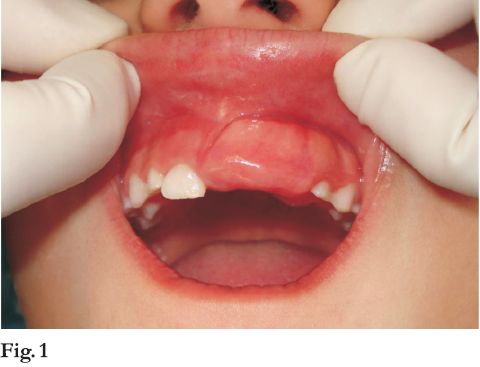

Diagnóstico clínico presuntivo: lesión hiperplásica reactiva. Se realiza biopsia incisional. Histopatológicamente debajo de mucosa pavimentosa crece una proliferación esencialmente fibromatosa caracterizada por presentar epitelio odontogénico en forma de largos cordones anastomosados entre si, adyacentes a material hialino, globular, con calcificación focal (fig. 8 y 9).

El diagnóstico histopatológico fue de tumor odontogénico periférico con los caracteres de un fibroma odontogénico con “glóbulos hialinos”.

En uno de los casos publicados en este artículo se destaca una variante histopatológica poco común y peculiar, descrita por Dunlap (12), que incluye gotas de un material hialino eosinófilo, débilmente positivo frente a marcadores histoquímicos para amiloide, en pleno tejido fibroso y relacionado a presencia de epitelio.

El origen de estas estructuras es incierta pero se han encontrado en otros tumores odontogénicos. Podría tratarse de una proteína de matriz de esmalte mas que amiloide (13).